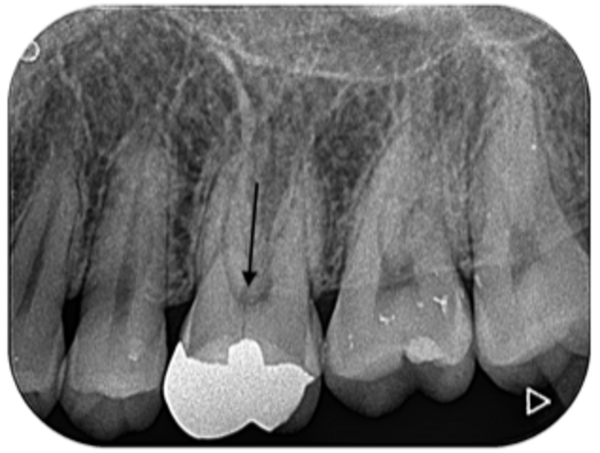

口腔内診察で左上6番目の歯が縦に割れていることがわかり、破折がどこまで続いているかを判断するためにX線を撮りました。こちらが初診時のX線写真になります。

歯の中央部が縦に破折していることがわかりました。

破折は歯髄腔(歯の神経がある部分)にまで及んでおり、当日は痛みを取るために神経を取る処置を行いました。加えて、歯科顕微鏡で歯の内部や破折部を直接確認しました。

破折は3つある歯根のうち1つに限局していました。